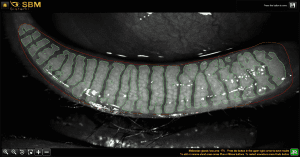

Photos are taken of the upper and lower eyelids to examine the meibomian gland morphology. The doctor can use these photos to assess gland health and analyse changes over time.